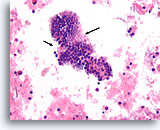

Afbeelding 13

Benigne, hyperplastisch/adenomatoïde nodule, schildklier FNA, celblok.

Het celblok dat overeenkomt met afbeelding 11-12 toont een duidelijk bijvoeging van micro- en macrofollikels. Er zijn twee kenmerken die voor een benigne nodule pleiten. Het eerste is dat de microfollikels afgeplat cytoplasma vertonen, vergeleken met de robuuster uitziende macrofolliculaire cellen (vergelijk de hoogte van het cytoplasma bij de twee pijlen). Een tweede kenmerk is de variatie in het uiterlijk van het colloïd tussen de verschillende follikels. Let op het oedemateuze colloïd in het ene follikel dat zich naast een follikel bevindt met dicht opeengepakt colloïd (open pijlen). Van benigne hyperplastisch/adenomatoïde nodulen wordt verwacht dat ze heterogeniteit vertonen, terwijl folliculaire neoplasmen monotoner zijn.

40X

Afbeelding 13

Benigne, hyperplastisch/adenomatoïde nodule, schildklier FNA, celblok.

Het celblok dat overeenkomt met afbeelding 11-12 toont een duidelijk bijvoeging van micro- en macrofollikels. Er zijn twee kenmerken die voor een benigne nodule pleiten. Het eerste is dat de microfollikels afgeplat cytoplasma vertonen, vergeleken met de robuuster uitziende macrofolliculaire cellen (vergelijk de hoogte van het cytoplasma bij de twee pijlen). Een tweede kenmerk is de variatie in het uiterlijk van het colloïd tussen de verschillende follikels. Let op het oedemateuze colloïd in het ene follikel dat zich naast een follikel bevindt met dicht opeengepakt colloïd (open pijlen). Van benigne hyperplastisch/adenomatoïde nodulen wordt verwacht dat ze heterogeniteit vertonen, terwijl folliculaire neoplasmen monotoner zijn.

40X